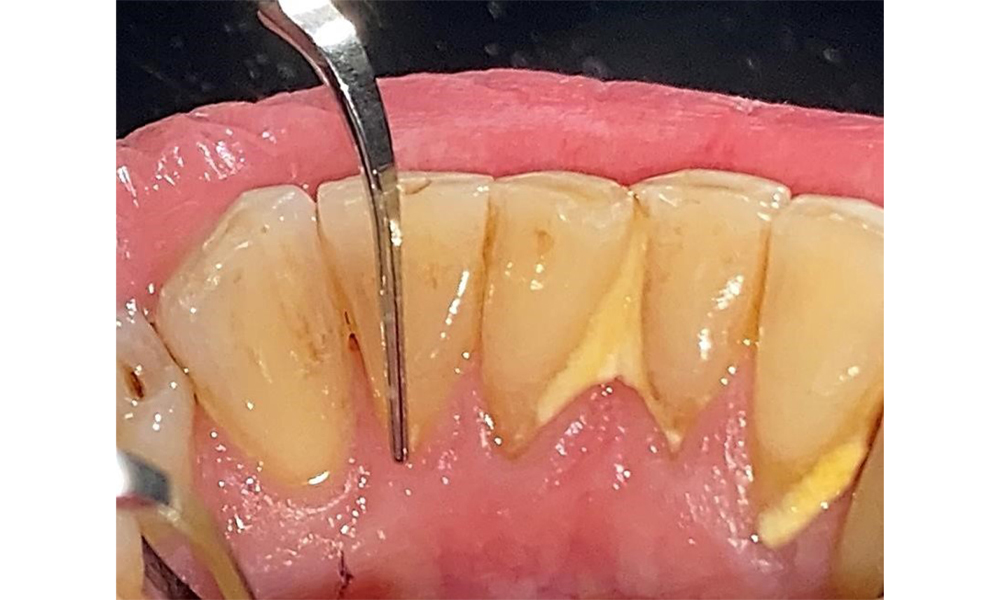

The patient has stage II, grade B periodontitis (5). At 1 to 3 mm, the clinical probing depths were within the physiological range. Localized probing depths of 5 mm were observed on the mesiopalatal aspects on both 17 and 27. There are generalized recessions of 1–3 mm with partial loss of the interdental papillae (Fig. 2, Fig. 3, Fig. 4)

The documentation of periodontal findings, including pocket depth probing and bleeding status, is mandatory during each dental appointment due to the presence of periodontitis (Fig. 8). This will record the individual therapeutic needs and facilitate a rapid response to any progression of the pre-existing periodontitis.

Detailed periodontal findings, including the documentation of pocket depths, bleeding on probing, recessions, furcation involvement and degree of loosening, must be examined annually.

This will ensure a rapid response to any potential progression of the pre-existing periodontitis. Examination of the hard tooth structure and root surfaces is also mandatory, since the presence of exposed root surfaces increases the risk of root caries.